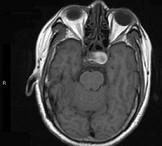

问题 男性,55岁,头痛一年余,两个小时前突然出现剧烈头痛,MRI检查如图所示,最可能的诊断为()

选项 A.垂体瘤 B.脑膜瘤 C.颅咽管瘤 D.垂体瘤并卒中 E.动脉瘤

答案 D